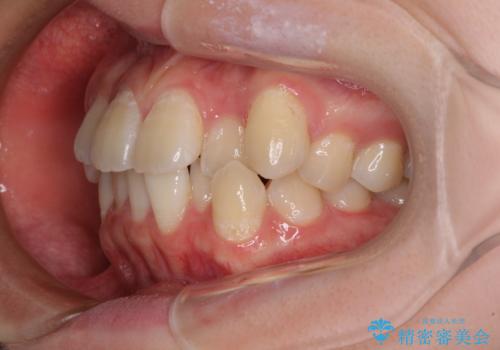

- 前歯のデコボコと八重歯を気にして来院された患者様です。

インビザラインでの治療を希望されていましたが、前歯のクロスバイトや下顎小臼歯の捻転が認められたため、インビザライン単独で治療を行うよりも、ワイヤー装置を併用した方が、治療期間の短縮やトラブル回避できると判断し、ワイヤー装置を併用することとしました。

まずはワイヤー装置により前歯のクロスバイトと下顎小臼歯の捻転を改善し、その後インビザラインにより全体を整える矯正治療を行うこととしました。

前歯のクロスバイトは、インビザラインでの改善中に前歯に過剰な力がかかり、歯髄壊死や歯肉退縮を引き起こすことがあります。また下顎小臼歯は寸胴型のため、捻転を排除することが難しいことが知られています。

それをワイヤー装置にて速やかに改善することで、トータルでの治療期間を短くすることができます。